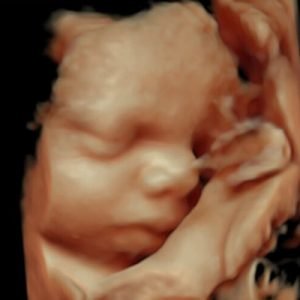

3D Υπερηχογράφημα